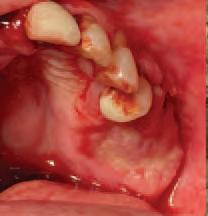

Issuu converts static files into: digital portfolios, online yearbooks, online catalogs, digital photo albums and more. Sign up and create your flipbook.